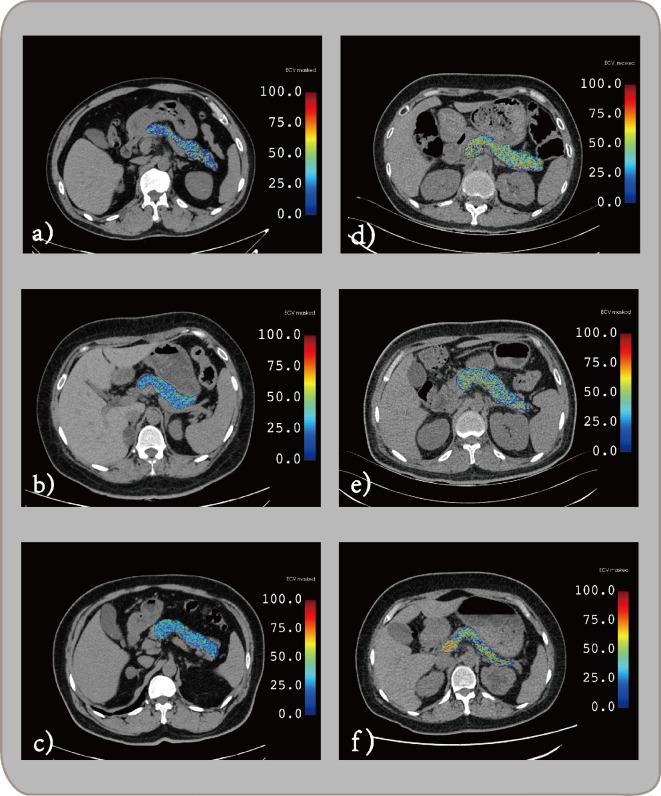

To develop noninvasive, opportunistic screening methods using routine abdominal enhanced CT imaging to derive an automated pancreatic extracellular volume fraction (AP-ECV) as a novel biomarker for evaluating microangiopathy in type 2 diabetes mellitus (T2DM).

A retrospective study was conducted on 320 patients with T2DM who underwent routine enhanced abdominal CT examinations. Microangiopathy refers to retinopathy, nephropathy or peripheral neuropathy in patients with diabetes. An automated method was developed to calculate AP-ECV values from enhanced abdominal CT images. The association between AP-ECV and T2DM microangiopathy was evaluated using univariate and multivariate logistic regression analyses. Then, assess the sensitivity, specificity, and area under the receiver operating characteristic curve (AUC) for AP-ECV's diagnostic ability in T2DM microangiopathy. Ordinal logistic regression estimated risk factors associated with the severities of microangiopathy, categorized into three levels.

AP-ECV and T2DM duration significantly increased in T2DM patients with microangiopathy (p < 0.01). The AUC for AP-ECV and T2DM duration were 0.767 and 0.761, respectively, with a combined AUC of 0.881. As AP-ECV increased (OR 1.406) and T2DM duration lengthened (OR 1.163), microangiopathy severity significantly escalated.